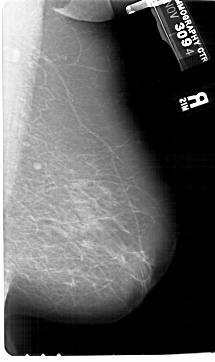

A_1108_1.LEFT_MLO

LEFT_MLO LINES 6781 PIXELS_PER_LINE 3676 BITS_PER_PIXEL 12 RESOLUTION 43.5 OVERLAY

FILE: A_1108_1.LEFT_MLO.OVERLAY

TOTAL_ABNORMALITIES 1

ABNORMALITY 1

LESION_TYPE CALCIFICATION TYPE PUNCTATE DISTRIBUTION CLUSTERED

ASSESSMENT 4

SUBTLETY 2

PATHOLOGY MALIGNANT

TOTAL_OUTLINES 1

BOUNDARY